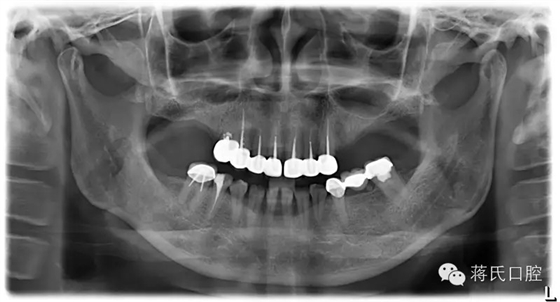

種植前X線(xiàn),左側(cè)外提升右側(cè)內(nèi)提升

患者情況女 49歲,三類(lèi)骨,右上區(qū)骨高度6毫米,寬度8毫米。左上區(qū)骨最低點(diǎn)1毫米,寬度3毫米